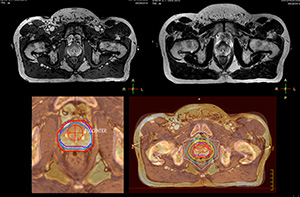

Impressive clinical benefits for prostate

“The biggest problem for CT-based planning, especially in prostate, is you can’t see the cancer very well,” says Dr. Stevens. “On CT it can be quite challenging to see the edge of the prostate especially at the apex. When the edge of the prostate can’t be delineated well on CT, radiation oncologists will increase their margins a little bit so they don’t miss it, but that can also increase toxicity.”

“Using MR, the prostate is well delineated. We quickly see the edges of cancerous tumors like in prostate cancer, and as normal structures can be defined, we can optimize the treatment plan to protect these organs and their normal function. This can potentially improve the outcome. And it improves workflow as well. We can contour more quickly, confident that the tumor is going to be in the field.”

“When a patient registers, first CT simulation and MR simulation are done, followed by CT-MR registration on Pinnacle3. Then the target and normal organ delineation is performed on MR images. Meanwhile we create a reference CT image for online treatment and localization correction. During the treatment phase we can perform additional MRI scans to visualize the anatomy changes and create an adaptive plan. This plan basically adapts the treatment plan to the changes.”